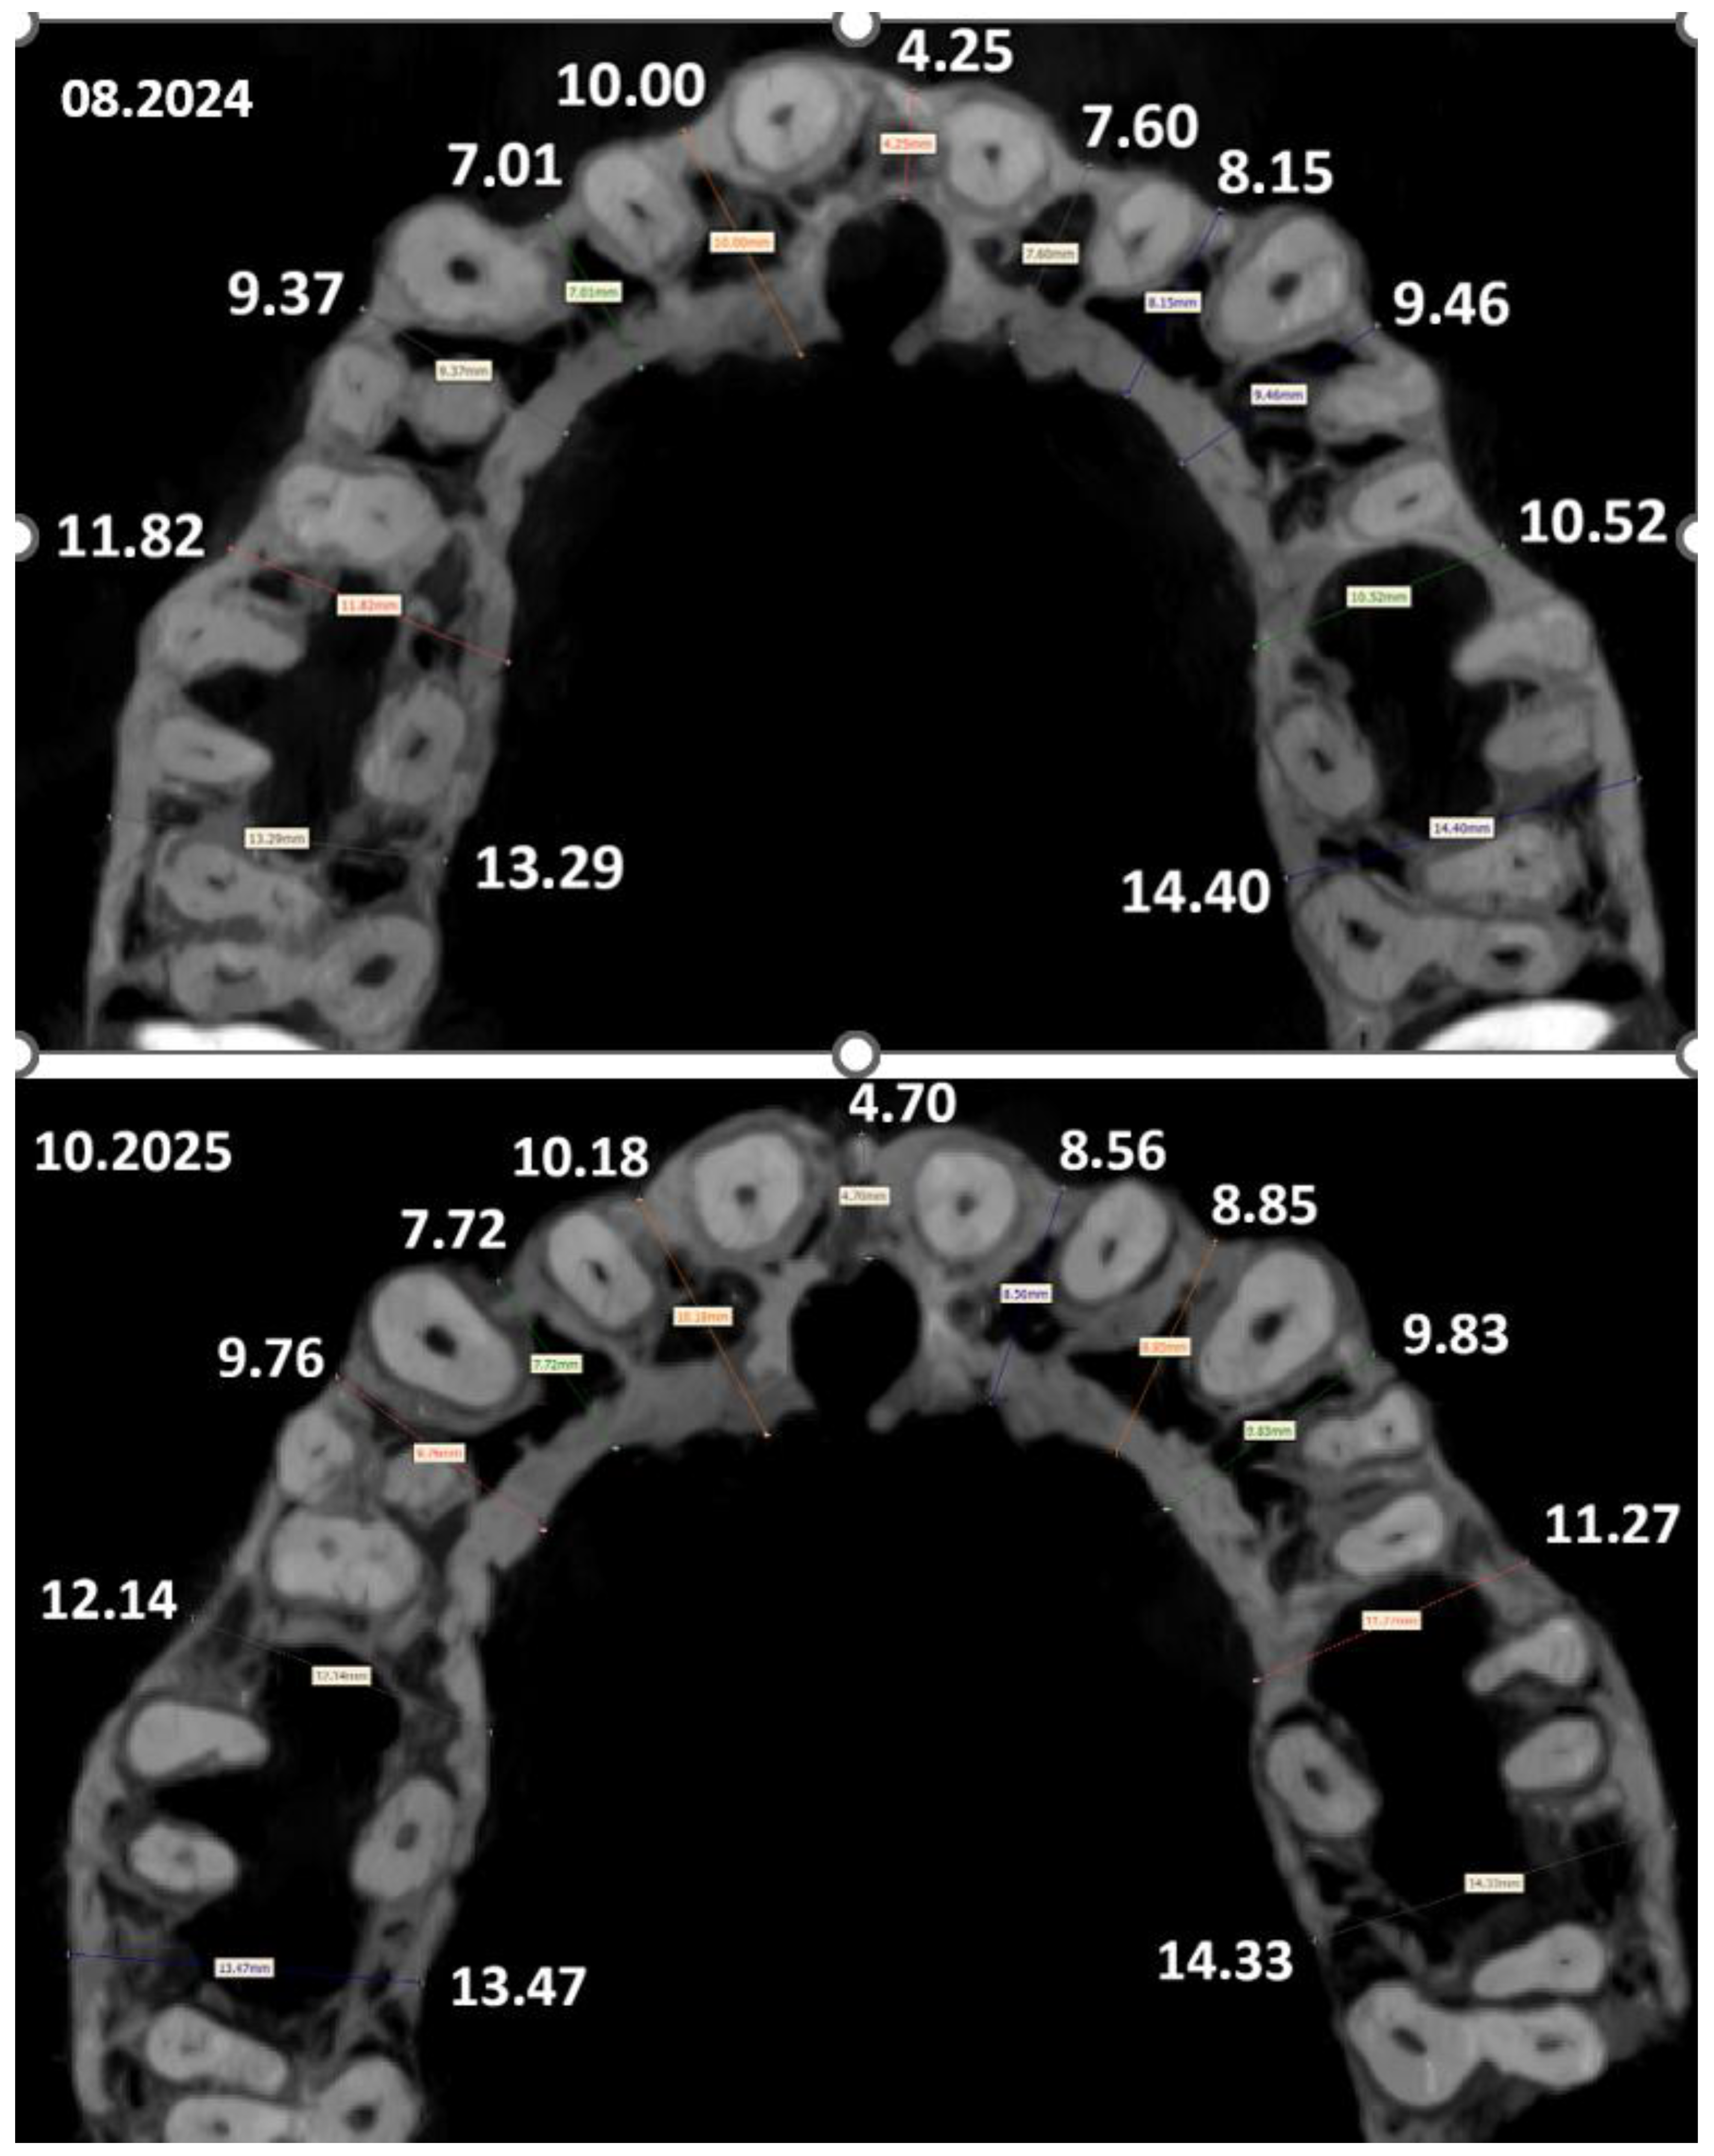

| Maxilla | |||

| Segment | August 2024 (mm) | October 2025 (mm) | Change (mm) |

| 1 | 11.82 | 12.14 | +0.32 |

| 2 | 9.37 | 9.76 | +0.39 |

| 3 | 7.01 | 7.72 | +0.71 |

| 4 | 10.00 | 10.18 | +0.18 |

| 5 | 4.25 | 4.70 | +0.45 |

| 6 | 7.60 | 8.56 | +0.96 |

| 7 | 8.15 | 8.85 | +0.70 |

| 8 | 9.46 | 9.83 | +0.37 |

| 9 | 10.52 | 11.27 | +0.75 |

| 10 | 14.40 | 14.33 | −0.07 |

| 11 | 13.29 | 13.47 | +0.18 |